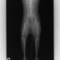

■ 症例20 ポメラニアン 8ヶ月 1.8kg

左右膝蓋骨脱臼 グレードⅢ

2ヶ月前から間欠的跛行が認められ、両膝の膝蓋骨脱臼整復術を行った。